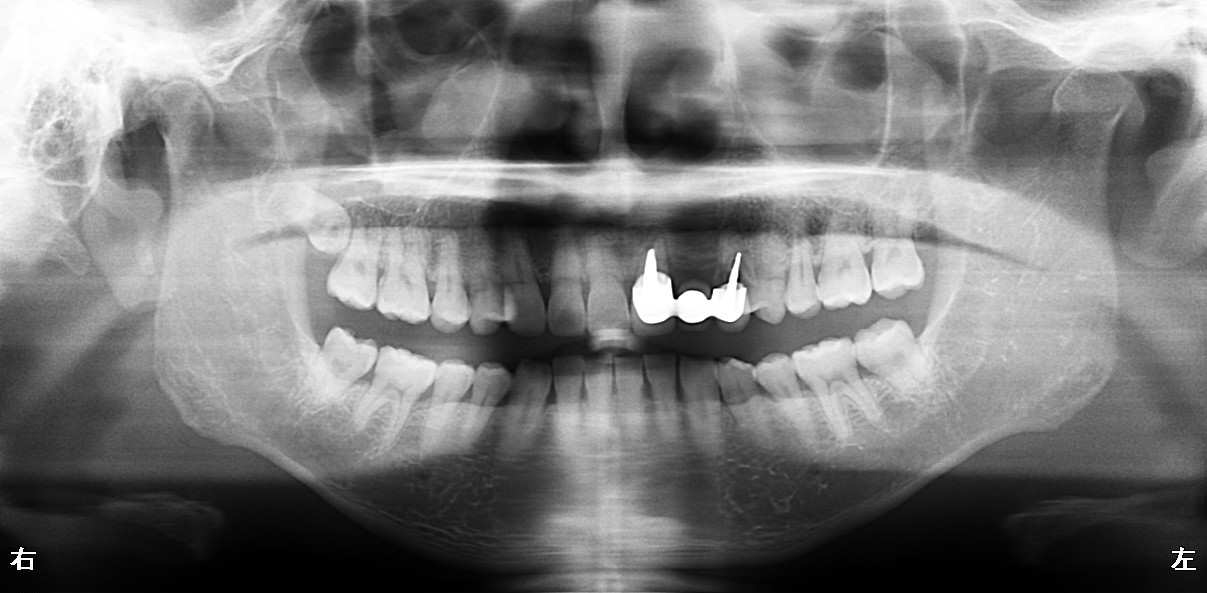

術前

抜歯後

最終的にインプラント治療を希望され、施術させて頂きました。